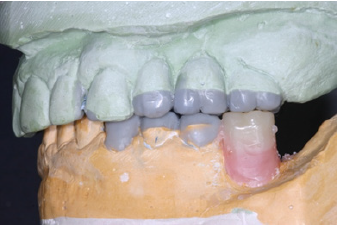

The final preparations were observed in two study casts to improve the parallelism and ensure accurate path of the insertion for the final prostheses. Final preparations and relining of the provisional restorations followed. Final impressions were performed using polyvinyl-siloxane (Aquasil, Dentsply, Germany) with the two-step double mixing technique (stock tray, double cord technique) in the maxilla. Mandibular impression was performed with an open tray technique combining implant and teeth abutments with polyether material (Impregum, 3M, USA). In next appointment the accuracy of final casts was examined and jaw relation recordings were performed. The position of maxillary cast was transferred with a Whip-Mix face bow and centric relation (CR) was registered with a custom made acrylic Lucia jig (anterior deprogrammer) and an implant retained base plate in the mandible to ensure accurate registration. Dental and implant abutments metal try-in were completed in two steps (Figure 16). After thorough verification of accuracy of fit and jaw registrations, ceramic veneering was checked for proper occlusion (Figure 17,18). Finally all restorations were cemented with adhesive resin cement (Panavia F2.0, Kuraray, Japan), except for the implant restorations which were cemented with a provisional cement (Temp-bond, Kerr, Germany).

Figure 16: Dental abutments metal try in the maxilla.